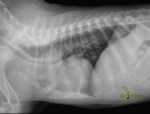

Pour vous guider dans vos diagnostics